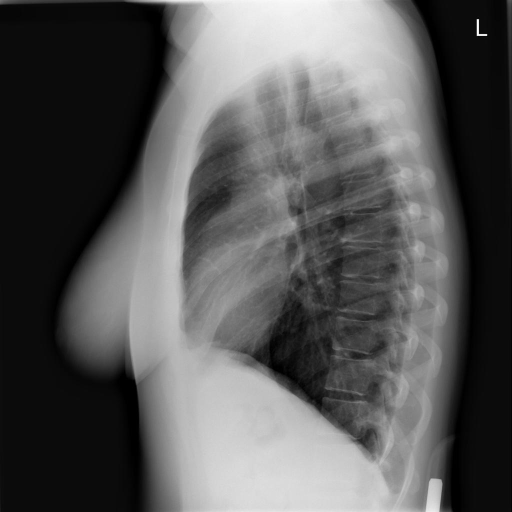

We compare our projected X-Rays with samples from the OpenI dataset for frontal and lateral views in Figure 5. The differences in the frontal view are due to the different positioning of the shoulder girdle. In the X-Rays, the arms are usually placed alongside the body, while in the projected images, the arms are raised due to the nature of the CT scan. In the lateral view, the X-Rays show a more comprehensive range of orientation and pose. However, the projected images, typically taken while the patient is lying down, result in similar poses between the different images. This leads to visual differences between images of female patients in both frontal and lateral views, such as the third column and second row of real X-Ray images and the first column and second row of projected images.